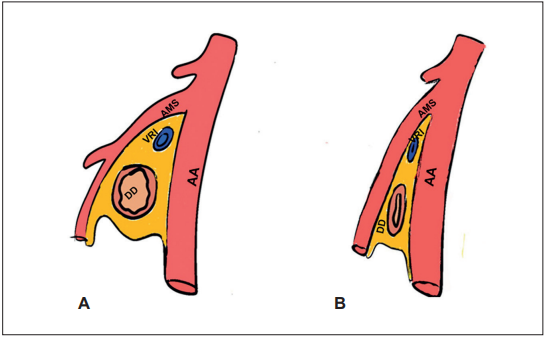

El síndrome de la arteria mesentérica superior (SAMS), también conocido como síndrome de Wilkie, es una obstrucción intestinal alta ocasionada por la compresión vascular de la tercera porción del duodeno por la arteria mesentérica superior sobre la aorta abdominal 1,2 (Figura 1). Es una patología poco frecuente, con una incidencia del 0,2 %, más común en mujeres (2:1) entre los 10 y 30 años, principalmente en pacientes con pérdida de peso rápido, que conlleva alta morbimortalidad 3,4.